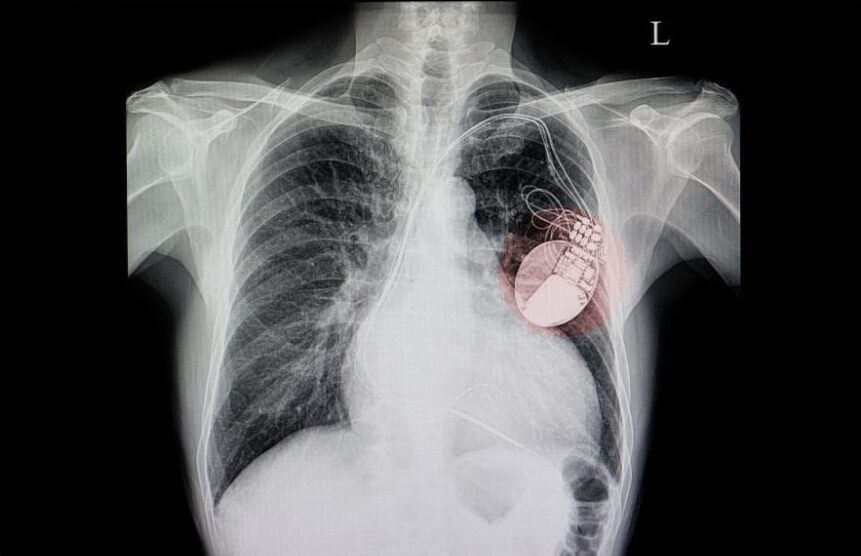

O procedimento é realizado com anestesia (sedação endovenosa) para que o implante seja totalmente indolor. As salas de cirurgia são isoladas, o ar é bacteriologicamente filtrado e o fluxo é laminar, praticamente eliminando o risco de infecções. Durante a cirurgia, são implantados eletrodos especiais no coração, que chegam até o marca-passo pelas veias.